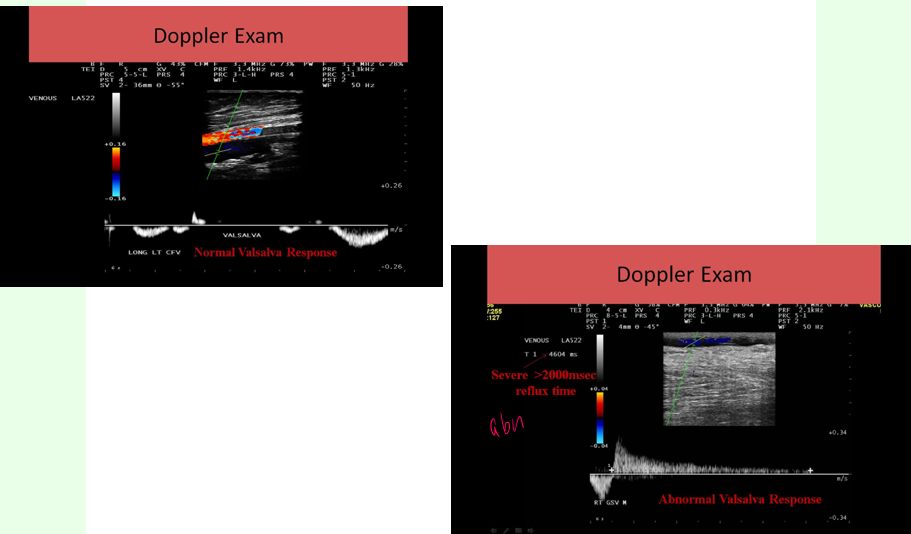

what are the nonvascular pathology findings during venous exams?

soft tissue edema - leg swelling

lymphedema

this shows

soft tissue edema

leg swelling

associated with CHF